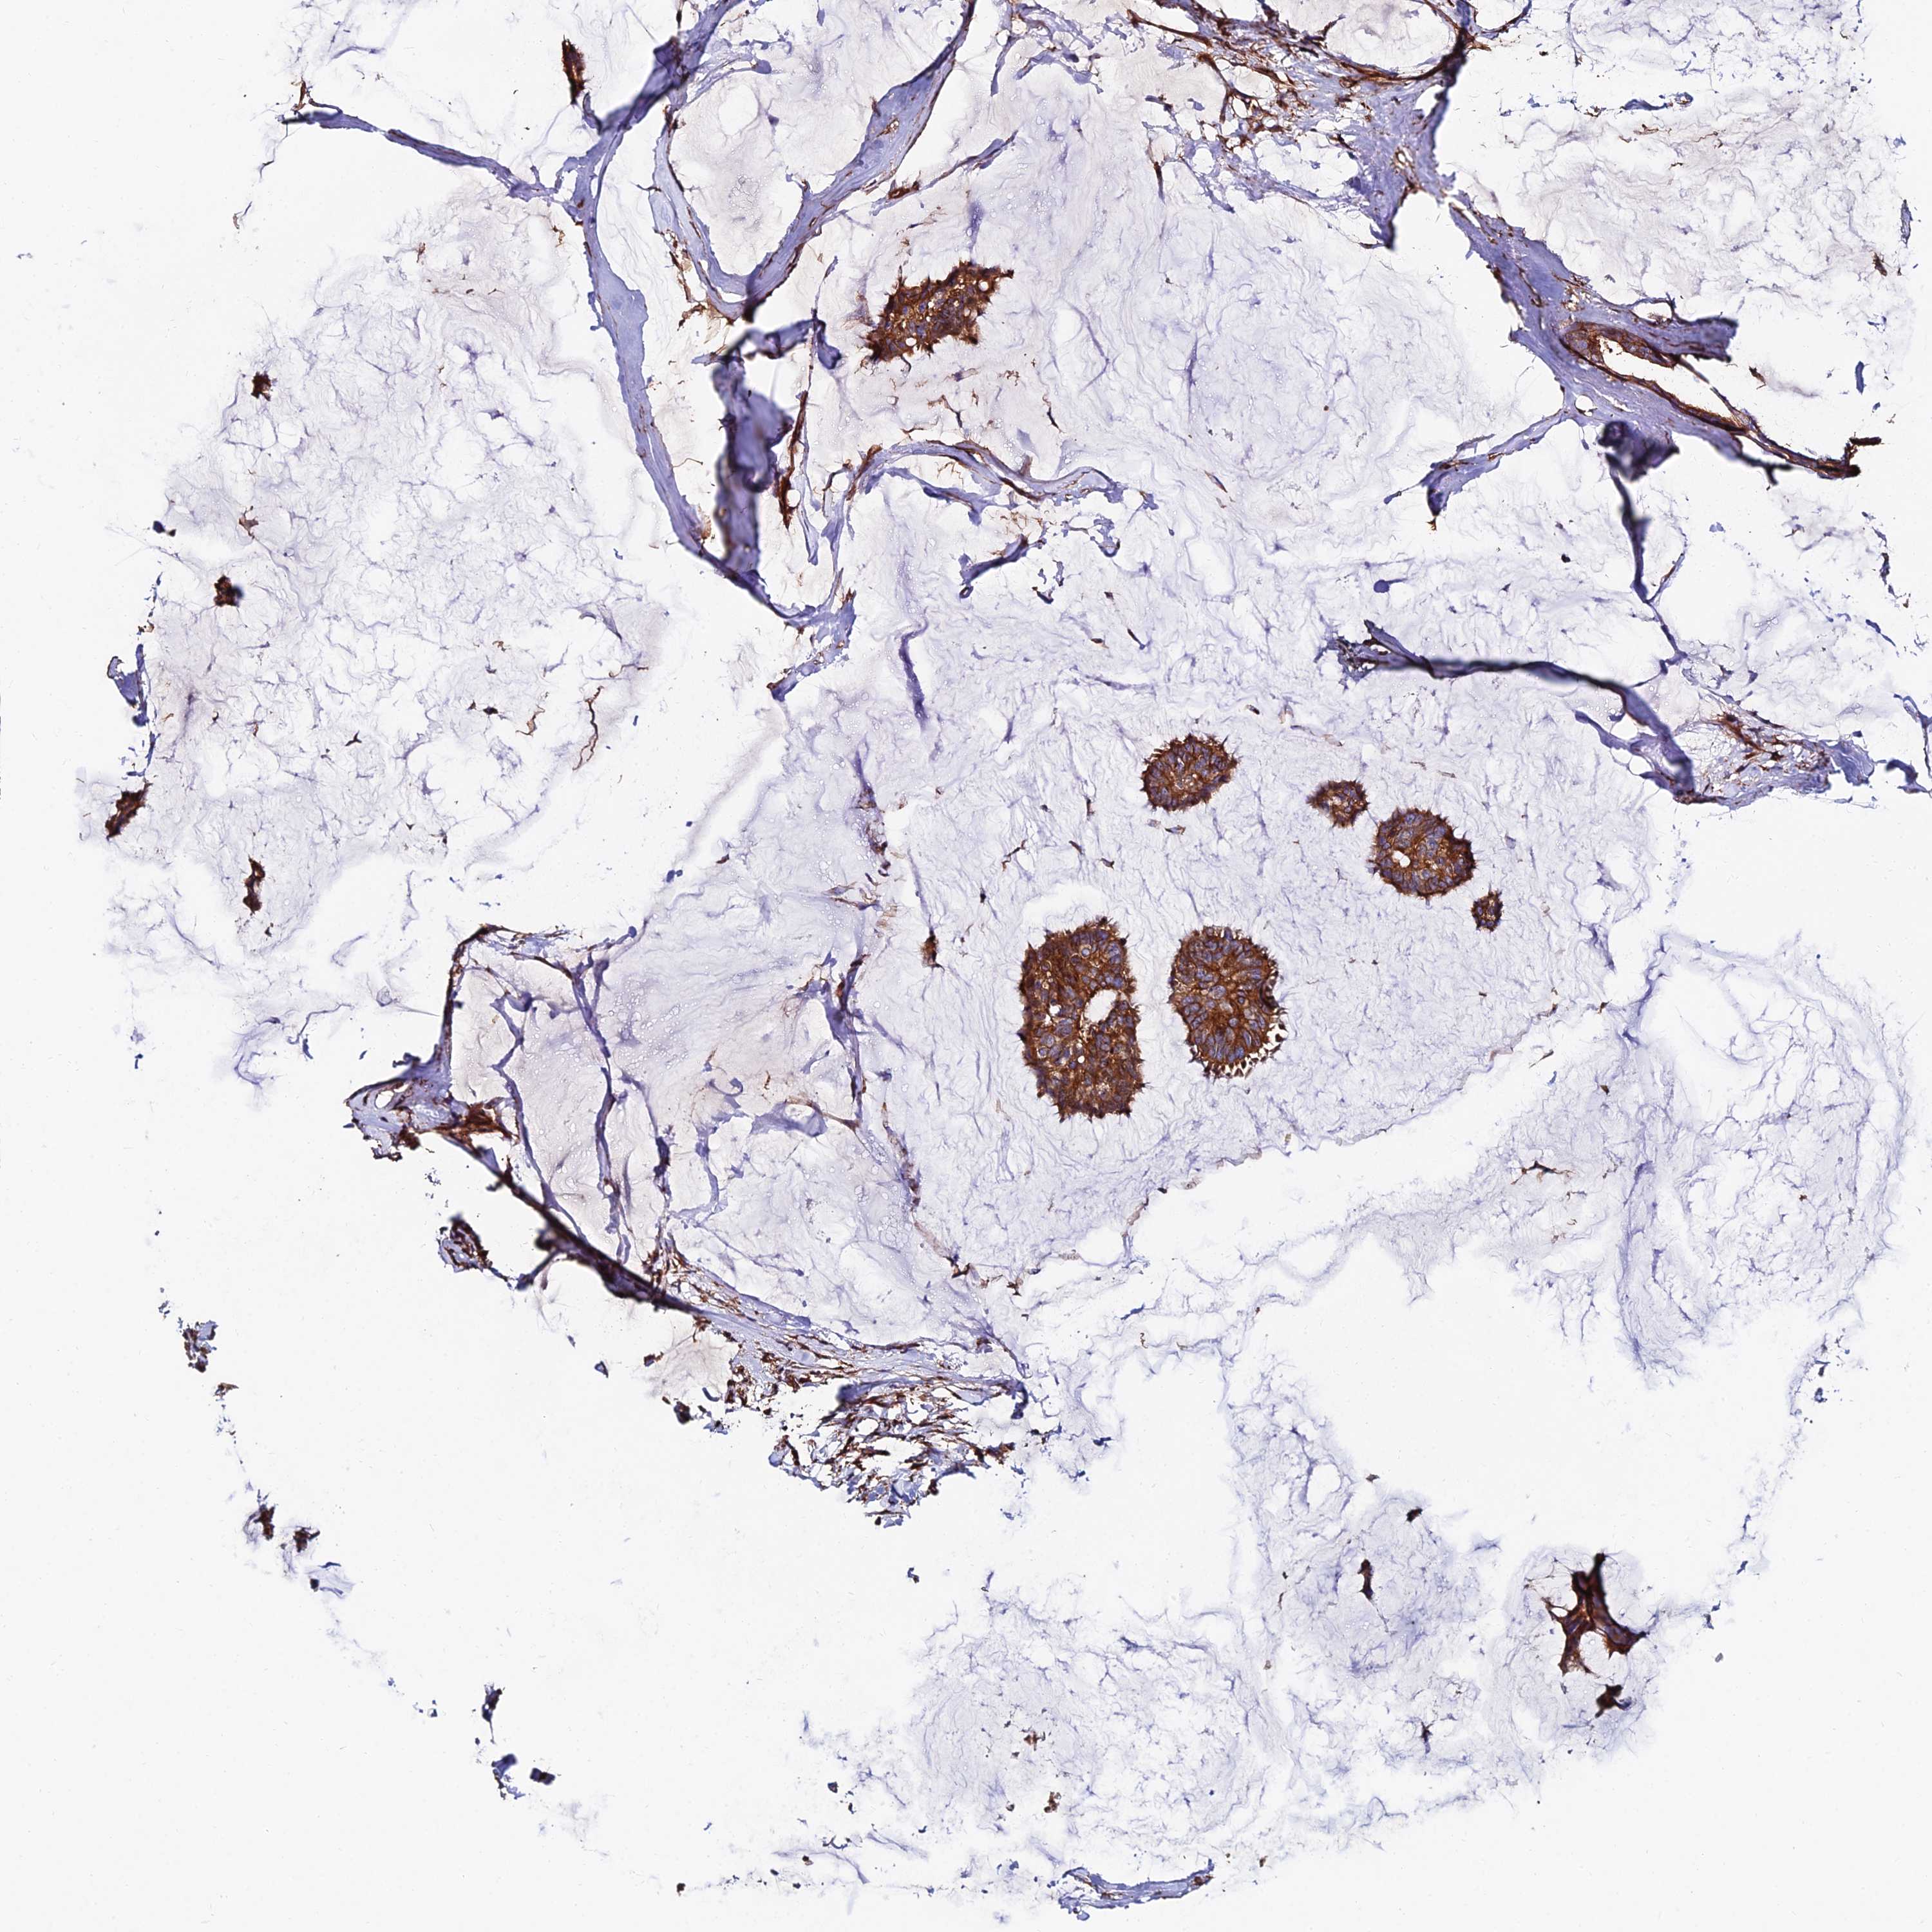

CANCER BREAST CANCER Show tissue menu

Breast cancer

Human cancer